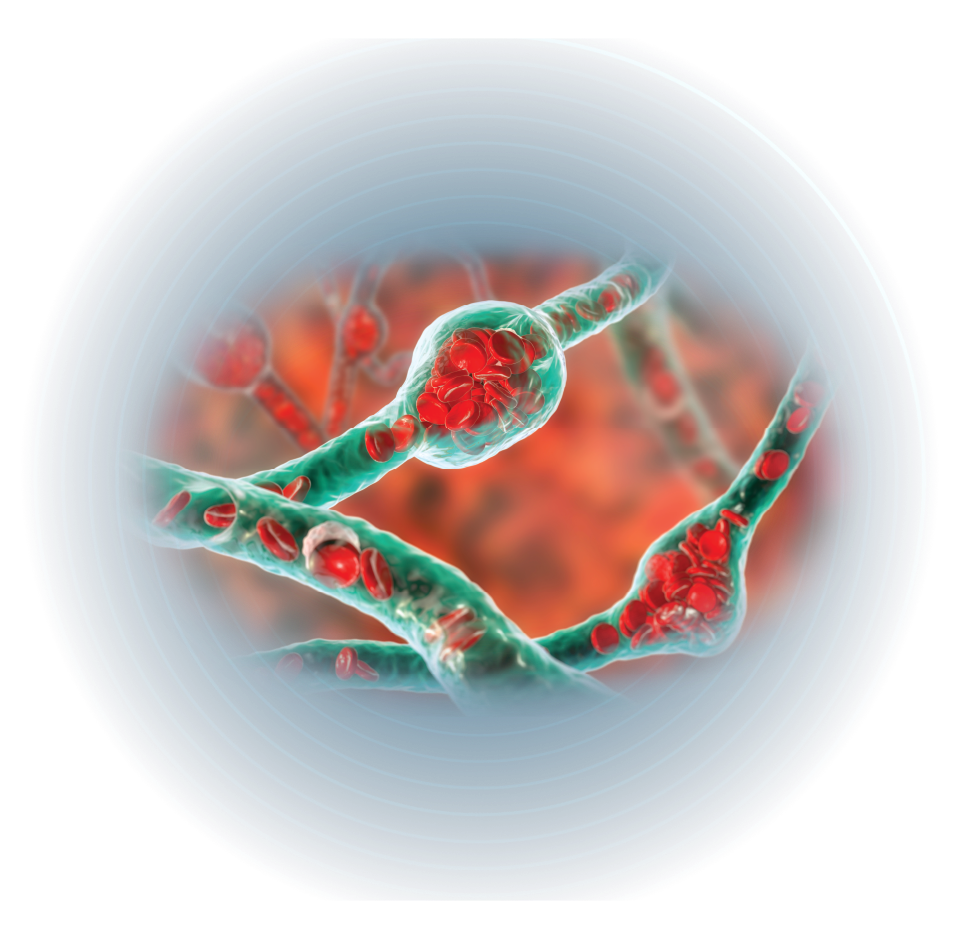

혈관 생성 및 조직 재생

rhBMP-2는 알칼리성 인산분해효소(ALP), 콜라겐 타입 I(COL1), 골소체 단백질

(osteocalcin, OC)과 같은 골 형성 발현을 유도하여 골기질 형성을 강화시키고 혈관 신생을

촉진하여 골 조직으로 산소와 영양 공급을 증가시킵니다.

더불어 친수성 표면은 혈소판 활성화를 통해 혈관 생성을 더 촉진합니다.